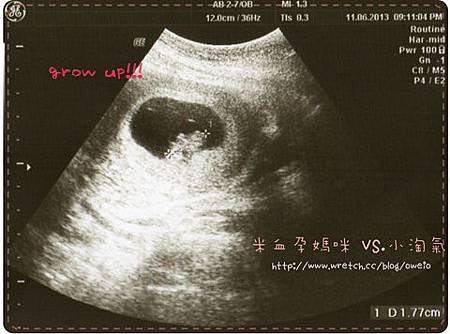

這次帶了相機,拍了好多小淘氣的模樣,但一樣只是小小白白的東東,不過~才8天,小淘氣又長大了0.74cm![]()

![]()